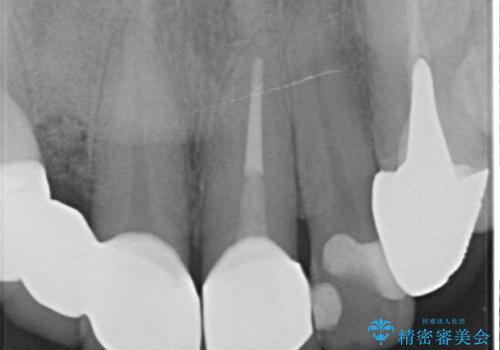

- 他院で治療したところ、右上2番目の歯の歯茎が下がってしまったので診て欲しいといらっしゃった方の症例です。

診査の結果右上2は歯根が破折しており、それが原因で骨及び歯肉の吸収が起きていました。

このまま右上2の抜歯を行うとさらに歯茎が下がる恐れがあったため、歯の挺出によって骨レベルを回復した上で抜歯し、歯槽堤保存術(抜歯窩に人工骨を填入する手術)を行いました。